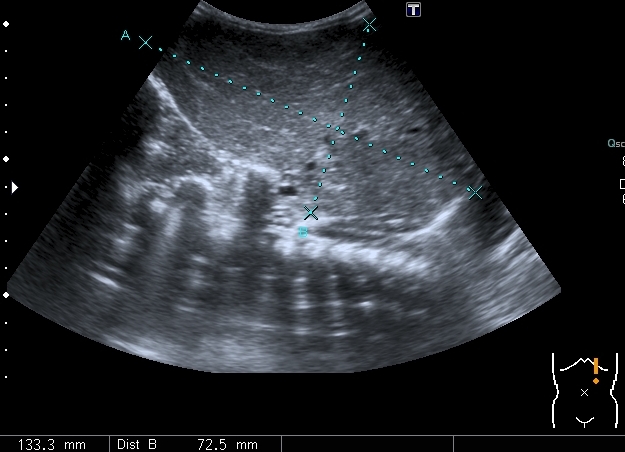

Ребёнок 2.5 месяцев, доставлен в связи с выявленным при очередном осмотре увеличением печени.

При УЗИ: печень резко увеличена, больше за счёт левой доли

Паренхима печени -гиперэхогенная , неоднородная, практически полностью замещена нодулярными образованиями, некоторые из них с "гало" и кальцификацией

Правый надпочечник представлен округлым гиперэхогенным тканевым образованием с участками кальцификации, гиповаскулярным по отношению к ткани печени и почки